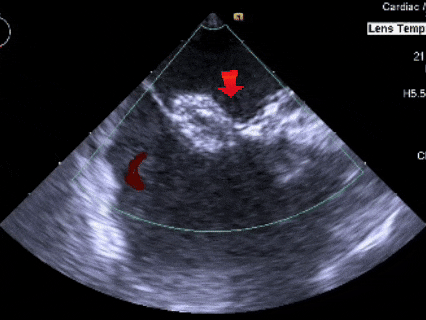

经食道超声所见:房间隔总长度约41mm。房间隔中部局部呈瘤样向右房膨出范围约11×19mm,房间隔中部回声中断约11×9mm,缺损上缘距房顶约17mm,缺损下缘距二尖瓣约10mm,缺损后下缘距下腔静脉约21mm,缺损后上缘距上腔静脉约13mm,短轴切面前残端0mm,后残端24mm。

超声提示:房间隔缺损(II孔型),房间隔膨胀瘤形成。

测量膨出瘤基底宽19.61mm,深7.00mm

房间隔总长44.22mm,缺损大小14.80mm

超声可见房间隔连续中断,彩色多普勒可见过隔血流